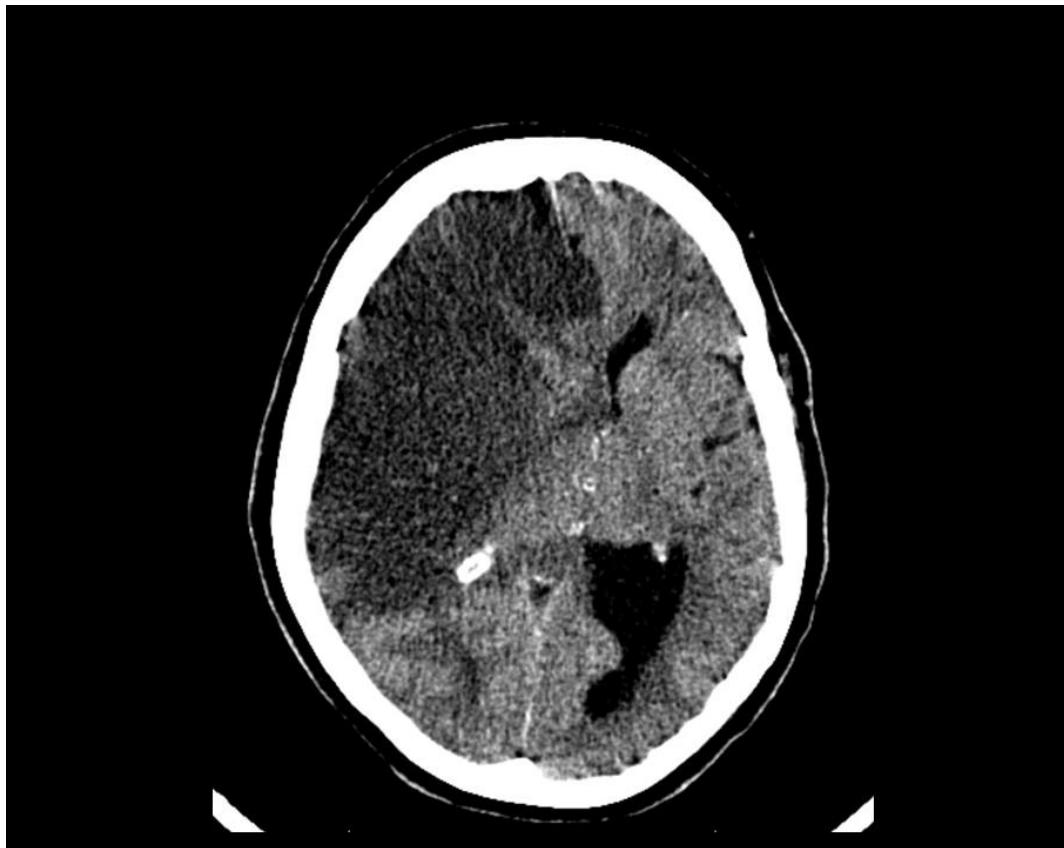

Brain CT Scan

Epidural Hematoma

- Diagnosis: Epidural Hematoma.

- CT Finding: Biconvex (Lens-shaped) hyperdensity; does not cross suture lines.

- Pathology: Usually arterial bleed (Middle Meningeal Artery).

- Note: May show midline shift.

Subdural Hematoma

- Diagnosis: Subdural Hematoma.

- CT Finding: Crescent (Sickle-shaped) hyperdensity; can cross suture lines.

- Pathology: Bleeding from bridging veins.

- Note: Higher density indicates acute bleeding.

Intracerebral Hemorrhage

- Diagnosis: Intracerebral Hemorrhage.

- CT Finding: Hyperdensity within the brain parenchyma.

Ischemic Stroke

- Clinical Case: Face drop, weakness.

- Management: Perform CT to rule out hemorrhage before giving thrombolytics. - if hemorrhagic to OR STAT